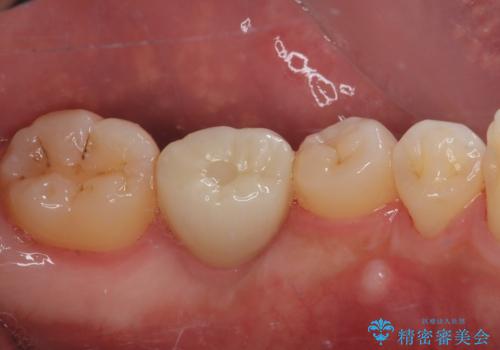

理想的な咬み合わせに改善した上で、インプラント補綴治療を行うこととしました。

部分矯正を行ったこと治療期間は長くなりましたが、違和感のない咬み合わせを達成することができました。